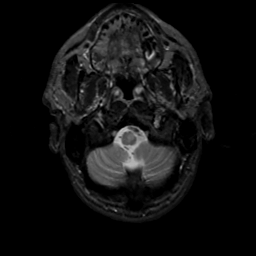

MR Study #6, March 17, 1991 -- Slice #4

[Home][Help][Clinical][Tour 1][Tour 2] Slice 4